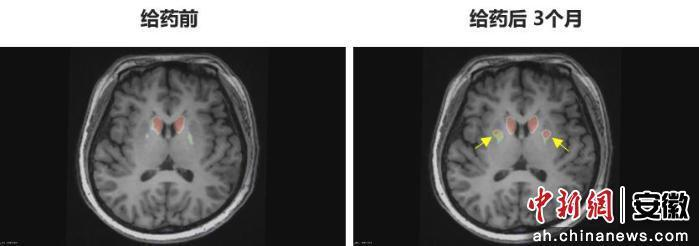

“身體不僵硬了,像正常人一樣?!崩钆啃χf(shuō)。多年的抖動(dòng)與“關(guān)期”徹底消失,她重新感受到身體的輕盈和心靈的自由。術(shù)后影像顯示,移植細(xì)胞已在腦內(nèi)成功定植并發(fā)揮功能,醫(yī)生稱這些“亮點(diǎn)”是新生多巴胺能神經(jīng)元的直接證據(jù)。

圖為李女士 PET-DAT/MRI融合圖像術(shù)前與術(shù)后三個(gè)月對(duì)比。

圖為李女士?PET-DAT/MRI融合圖像術(shù)前與術(shù)后三個(gè)月對(duì)比。